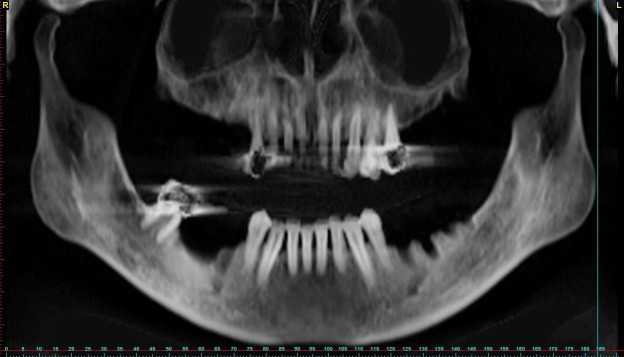

Фото Рак Нижней

Фото Рак Нижней 115 фото